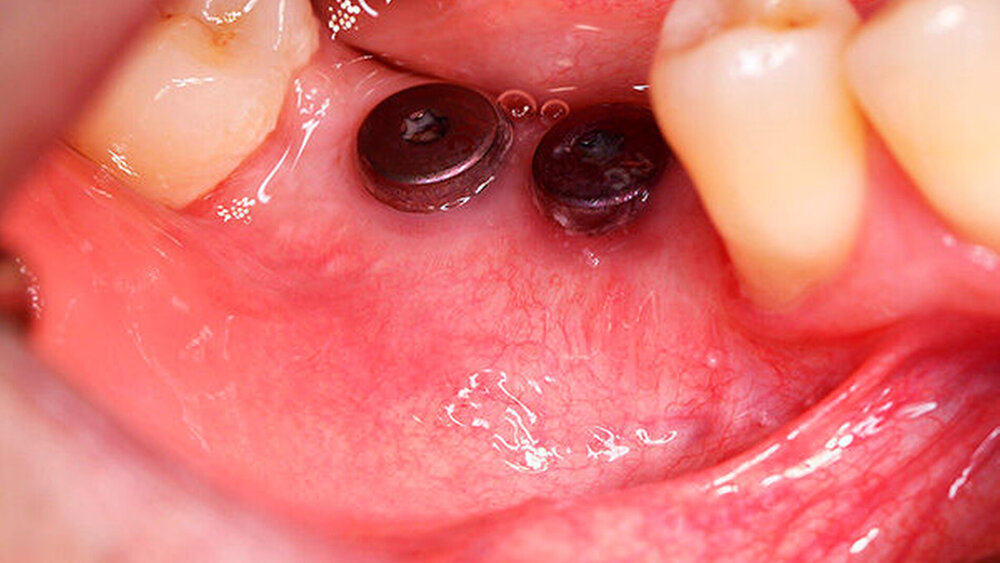

Nach missglückter Augmentation im rechten Oberkiefer stellte sich ein 42-jähriger Patient in unserer Praxis vor. Für die gewünschten Implantate im rechten Oberkiefer regio 16 und 17 war vertikal deutlich zu wenig Knochen vorhanden. Ein Sinuslift hätte zwar die Höhe des Knochens wieder hergestellt, die prothetische Position der Zahnkronen wäre aber somit in einer Infraokklusion zu liegen gekommen oder die Implanatkronen hätten völlig überdimensioniert werden müssen. Daher entschied sich der Patient für die Rekonstruktion mittels allogenen CAD/CAM-Knochenblocks. Das Prozedere gestaltete sich wie in Fallbeispiel 1. Auch die Einheilzeiten wurden entsprechend eingehalten.

Ein 29-jähriger Patient stellte sich mit einer massiven Alveolarkammatrophie im rechten Unterkiefer in unserer Praxis vor. Diese lag in langen Jahren der Zahnlosigkeit begründet. Eine Beckenkammaugmentation kam für den Patienten nicht in Betracht. Dennoch wünschte er die Versorgung mit festsitzendem Zahnersatz. Nach ausführlicher Beratung entschied sich auch dieser Patient für eine Augmentation mit einem patientenindividualisierten allogenen CAD/CAM-gefertigten Knochenblock. Die DICOM-Daten des Unterkiefer-DVTs wurde an die Firma Zimmer gesendet, und es erfolgten wie im oben beschriebenen Fall eine virtuelle Planung und das virtuelle Design des allogenen Knochenblocks anhand der geplanten Implantatpositionen. Nach der üblichen Kontrolle und Freigabe des Chirurgen erfolgte die eigentliche Fertigung und Übersendung des Knochenblocks in die Praxis. Die Augmentation erfolgte auch in diesem Fall in Vollnarkose unter antibiotischer Abschirmung perioperativ mit Ampicillin. Die Schnittführung im Unterkiefer unterscheidet sich von der Sockelschnittführung im Oberkiefer aufgrund der Anatomie (N. mentalis). Auch bei diesem Patienten wurde eine tief im Vestibulum liegende bogenförmige Inzi‧sion durchgeführt, jedoch ohne die vertikalen Entlastungen. Nach streng subperiostaler Präparation erfolgte die Darstellung des N. mentalis. Die Vorbereitung des Spenderbetts sowie die Wässerung, Einpassung und Befestigung des allogenen Knochenblocks gestalteten sich wie im Fallbeispiel 1. Die Heilzeit des Knochenblocks dauerte ebenfalls sechs Monate. Zwei Implantate (Straumann) wurden nach krestaler Schnittführung in Lokalanästhesie eingebracht und heilten subgingival binnen drei Monaten ein. Aufgrund des massiven Volumenzuwachses war auch ebenfalls eine Vestibulumplastik im Zuge der Implantatfreilegung notwendig. Das Prozedere verlief ebenfalls wie im Fallbeispiel 1. Das freiliegende Gewebe wurde mit einer Kollagenmatrix abgedeckt. Dadurch konnte die Breite der befestigten Gingiva deutlich verbreitert werden.